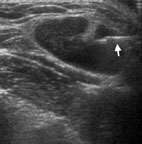

我們耳鼻喉科常接到其它科醫師因頸部切片後轉診要進行局部檢查的病患 (圖1),一看就發現在鼻咽部 (圖2)有明顯的腫瘤,以內視鏡鼻咽部切片證實為鼻咽癌,類似這種鼻咽癌的患者是不需要進行頸部腫塊的切片手術。所以無論如何,只要有頸部的腫塊應該馬上由專業的耳鼻喉科醫師進行詳細的頭頸部局部檢查,不宜冒然的進行頸部腫塊的切片。

圖2. 李先生在鼻咽部有明顯的腫瘤,鼻咽部切片證實為鼻咽癌